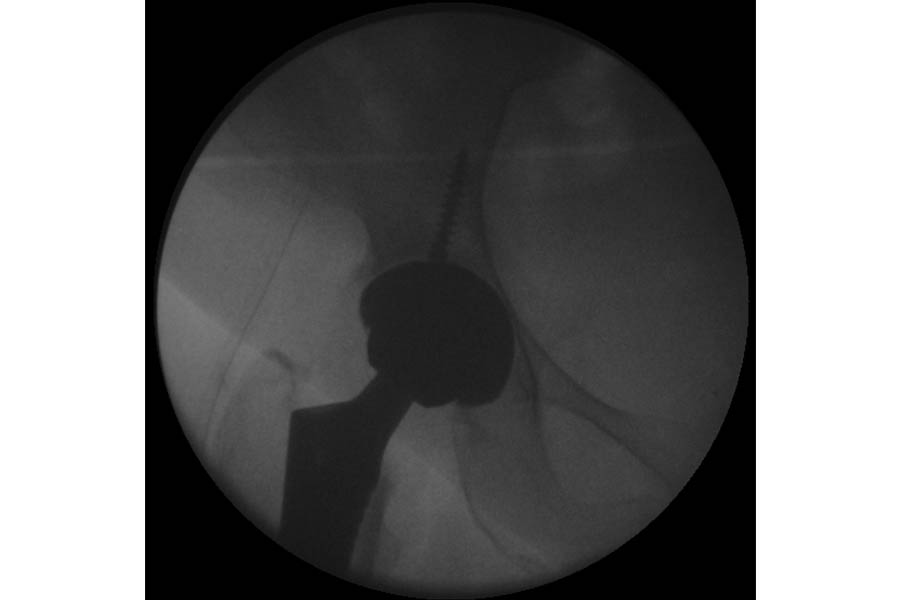

Total Hip Replacement

Case 1